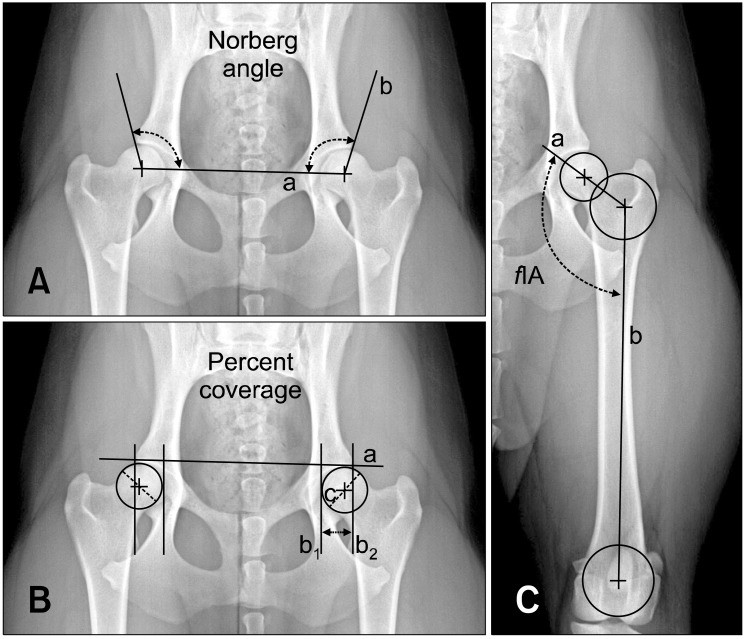

Рентген ТБС: Нормальные показатели

Раздел: Необычные решения